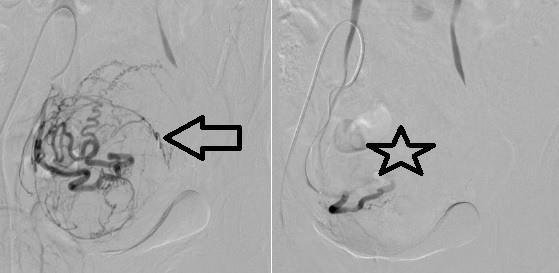

Hình 4: Minh họa động mạch tử cung và u xơ trước sau nút mạch chọn lọc |

Hình 5. Hình ảnh MRI u xơ tử cung trước và sau nút mạch động mạch tử cung (UAE), vị trí khối u được đánh dấu bằng mũi tên đỏ. A. Trước can thiệp MRI cho thấy khối u xơ tử cung, tín hiệu điển hình của u xơ, trước khi thực hiện nút mạch động mạch tử cung. B. Sau can thiệp MRI sau điều trị cho thấy khối u giảm tưới máu / giảm bắt thuốc, gợi ý thiếu máu và hoại tử sau nút mạch. |